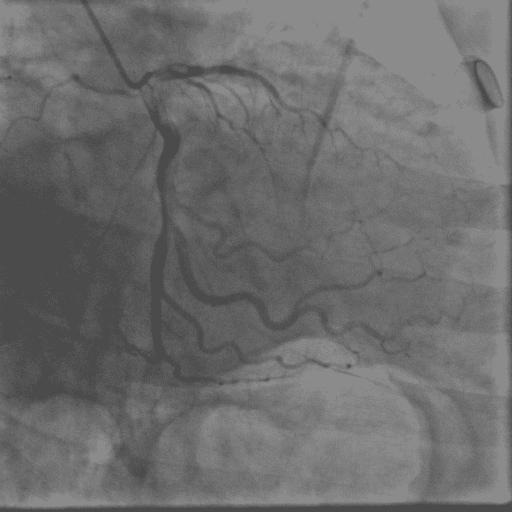

如果还是不相信,那就做“冠脉造影术”,是检查心脏血管有没有狭金标准!如果你的血管一点也没有狭窄,何来的心肌缺血呢?也就是说,起码血管性的因素可以排除。

冠脉造影术中血管看得非常清楚!